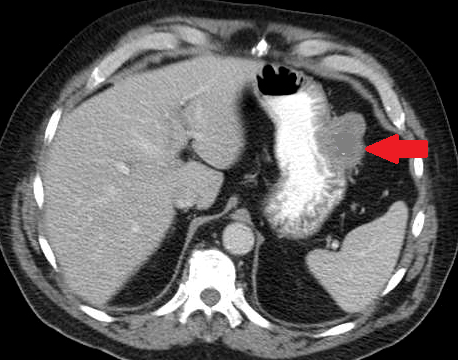

Contrast-enhanced CT of the abdomen, revealed a grossly distended stomach with mild diffuse thickening of its wall (red arrow)